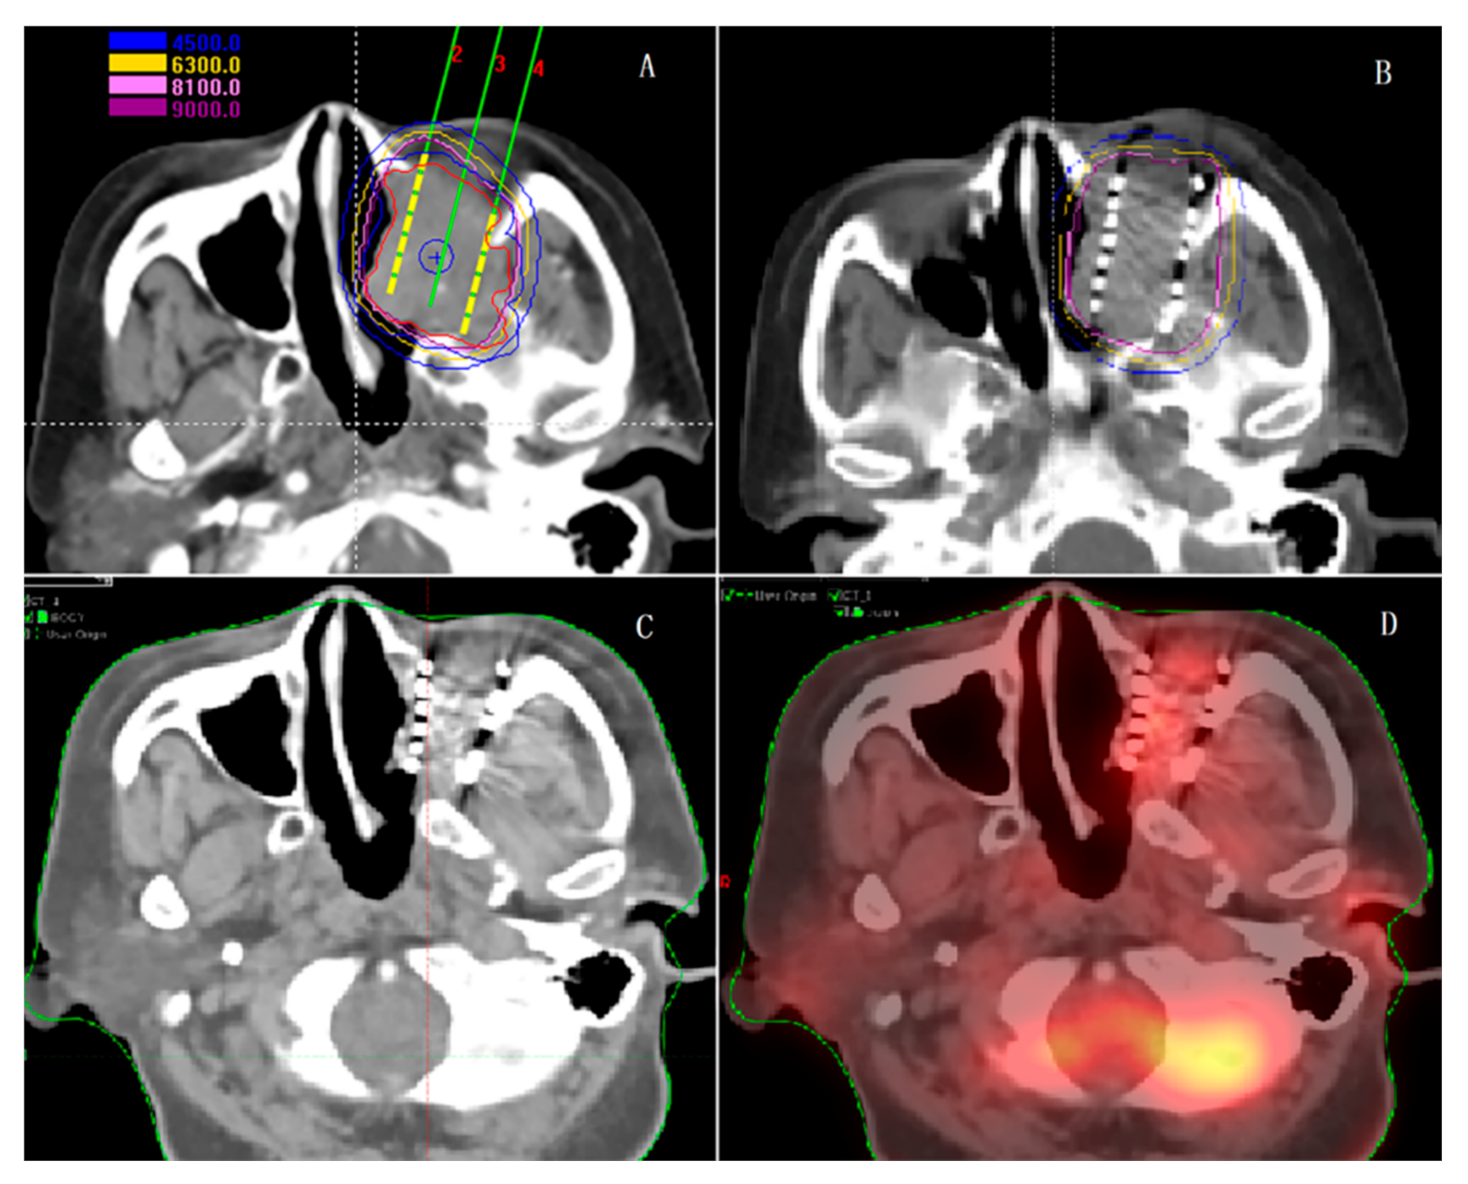

5.2. Application of SABT in Lung Cancer Patients

- Pang, H.; Wu, K.; Shi, X.; Tang, T.; Sun, X.; Yang, B.; Wu, J.; Lin, S. Hypofractionated (192)Ir source stereotactic ablative brachytherapy with coplanar template assistance in the primary treatment of peripheral lung cancer. J. Contemp. Brachyther. 2019, 11, 370–378. [Google Scholar] [CrossRef]

- Shi, X.X.; Pang, H.W.; Ren, P.R.; Sun, X.Y.; Wu, J.B.; Lin, S. Template-assisted (192)Ir-based stereotactic ablative brachytherapy as a neoadjuvant treatment for operable peripheral non-small cell lung cancer: A phase I clinical trial. J. Contemp. Brachyther. 2019, 11, 162–168. [Google Scholar] [CrossRef] [PubMed]

- Ji, Z.; Sun, H.; Jiang, Y.; Guo, F.; Peng, R.; Fan, J.; Wang, J. Comparative study for CT-guided 125I seed implantation assisted by 3D printing coplanar and non-coplanar template in peripheral lung cancer. J. Contemp. Brachytherapy 2019, 11, 169–173. [Google Scholar] [CrossRef]